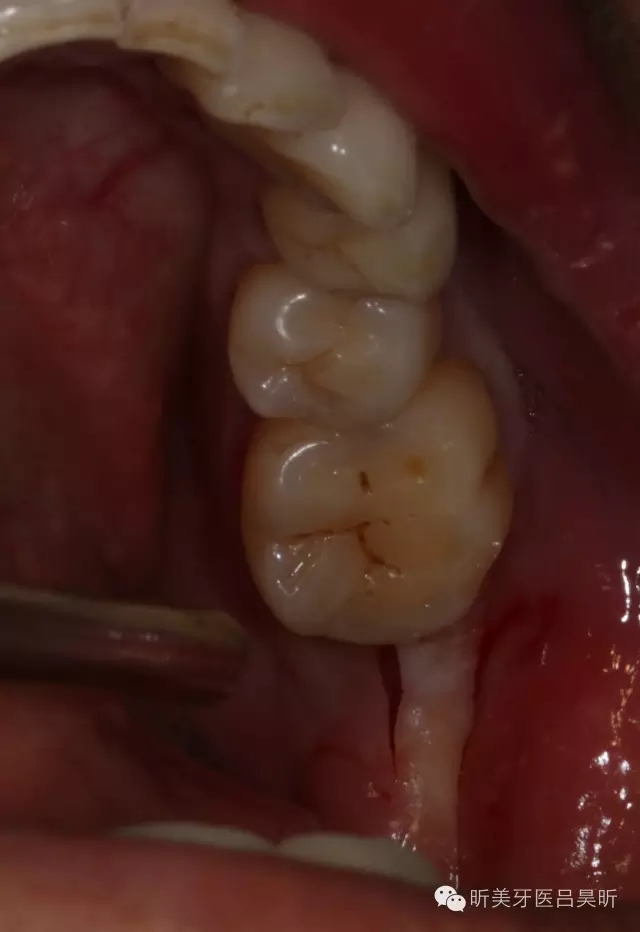

患者,男性,47缺失兩年。

術(shù)前口內(nèi)檢查,可見牙槽骨寬度良好,角化齦量適中